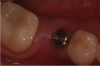

Fig. 19 through Fig. 24 The radiographic guide in place (19); the CBCT scan was taken with the guide seated in the mouth (20); after planning and milling the drill guide was inserted (21), guide in mouth with key and 2-mm bur (handpiece removed for photograph, 22), postoperative x-ray (23), immediate postoperative photograph of healing abutment (24). Surgery was done through tissue punch.